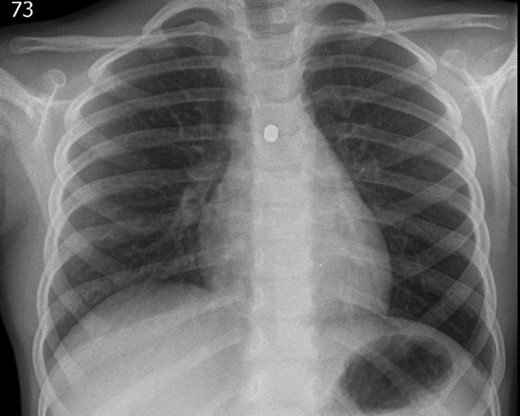

A 3-year-old girl was referred to the asthma clinic with a 3-month history of morning cough and wheeze. She was seen multiple times by her general practitioner (GP) who initially diagnosed her with upper respiratory tract infection. Her symptoms persisted despite salbutamol inhaler treatment so the GP organised a chest x-ray (CXR) (Fig. 1). It was reported that the left lung was translucent with reduced peripheral lung markings: finding consistent with asthma with bronchial plugging or a post infective bronchiolitis. It also showed a round radio-opaque FB over the left main bronchus. However, this was labelled as ‘Clothing Artefact’ on the actual radiograph and therefore did not alarm the GP or the reporting radiologist. A repeated PA CXR (Fig. 2) was undertaken in the asthma clinic where all clothes and hair were removed from the thorax. This confirmed the presence of a metallic FB in the left main bronchus and the patient was immediately admitted for bronchoscopy and removal of the FB.

Initial posterior–anterior chest x-ray (CXR) demonstrated a translucent left lung with reduced peripheral lung markings. There is also a dense rounded foreign body projected over the left main bronchus. A label of ‘CLOTHING ARTEFACT’ was placed in the left upper corner of this CXR.